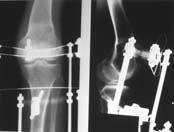

Пациент В. 53 лет, травма в феврале 2009. ДЗ. Открытый оскольчатый перелом нижней трети голени. При боли поступлении выполено ПХО, аппарат Илизарова. В последующем проводили ВХО, резекция костных отломков, укорочение 6 см, рана зажила. Была выполнена остеотомия большеберцовой кости в проксимальном отделе, резекция. Производилось тракция. На последних рентгенограммах выявлено, что одновременно с "выращиванием" регенерата произошло низведение надколенника на длину выращенного регенерата. Клинически: активное разгибание сохранено, объем движений в колене 180-110 градусов. Черными стрелками обозначен верхний край надколенника с одной и с другой стороны. Красная стрелка обозначает пальпируемую связку надколенника. Причина - остеотомия выше места прикрепления связки надколенника. Вопрос: была ли у кого подобная ситуация? Что делать? При первом обдумывании приходит решение: отсечение места прикрепления связки надколенника с костным блоком, перемещение на "правильное" место, укорочение сухожилия четырехглавой мышцы.

По снимкам - плотность регенерата хорошая, сложностей с фиксацией в него костного "основания" быть не должно.

К сожалению, подобное осложнение "нет-нет да и возникает" при удлинении, коррекции деформации голени. В англоязычной литературе оно описано как "patella baja". Один из вариантов лечения - проксимальное перемещение надколенника приемами чрескостного остеосинтеза.

По-моему, надколенник низвелся на величину, гораздо меньшую удлинению.

Я бы уменьшил диастаз между фрагментами сантиметра на два. Судя по снимкам, регенерат это может позволить.